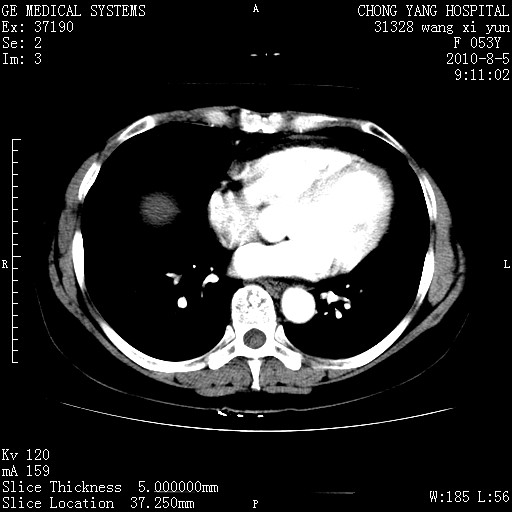

标题: CT28214:F41Y 血尿二十天,建议盆腔平扫加增强。

1)考虑肝左叶胆管细胞癌。2)脂肪肝。

支持胆管细胞ca。